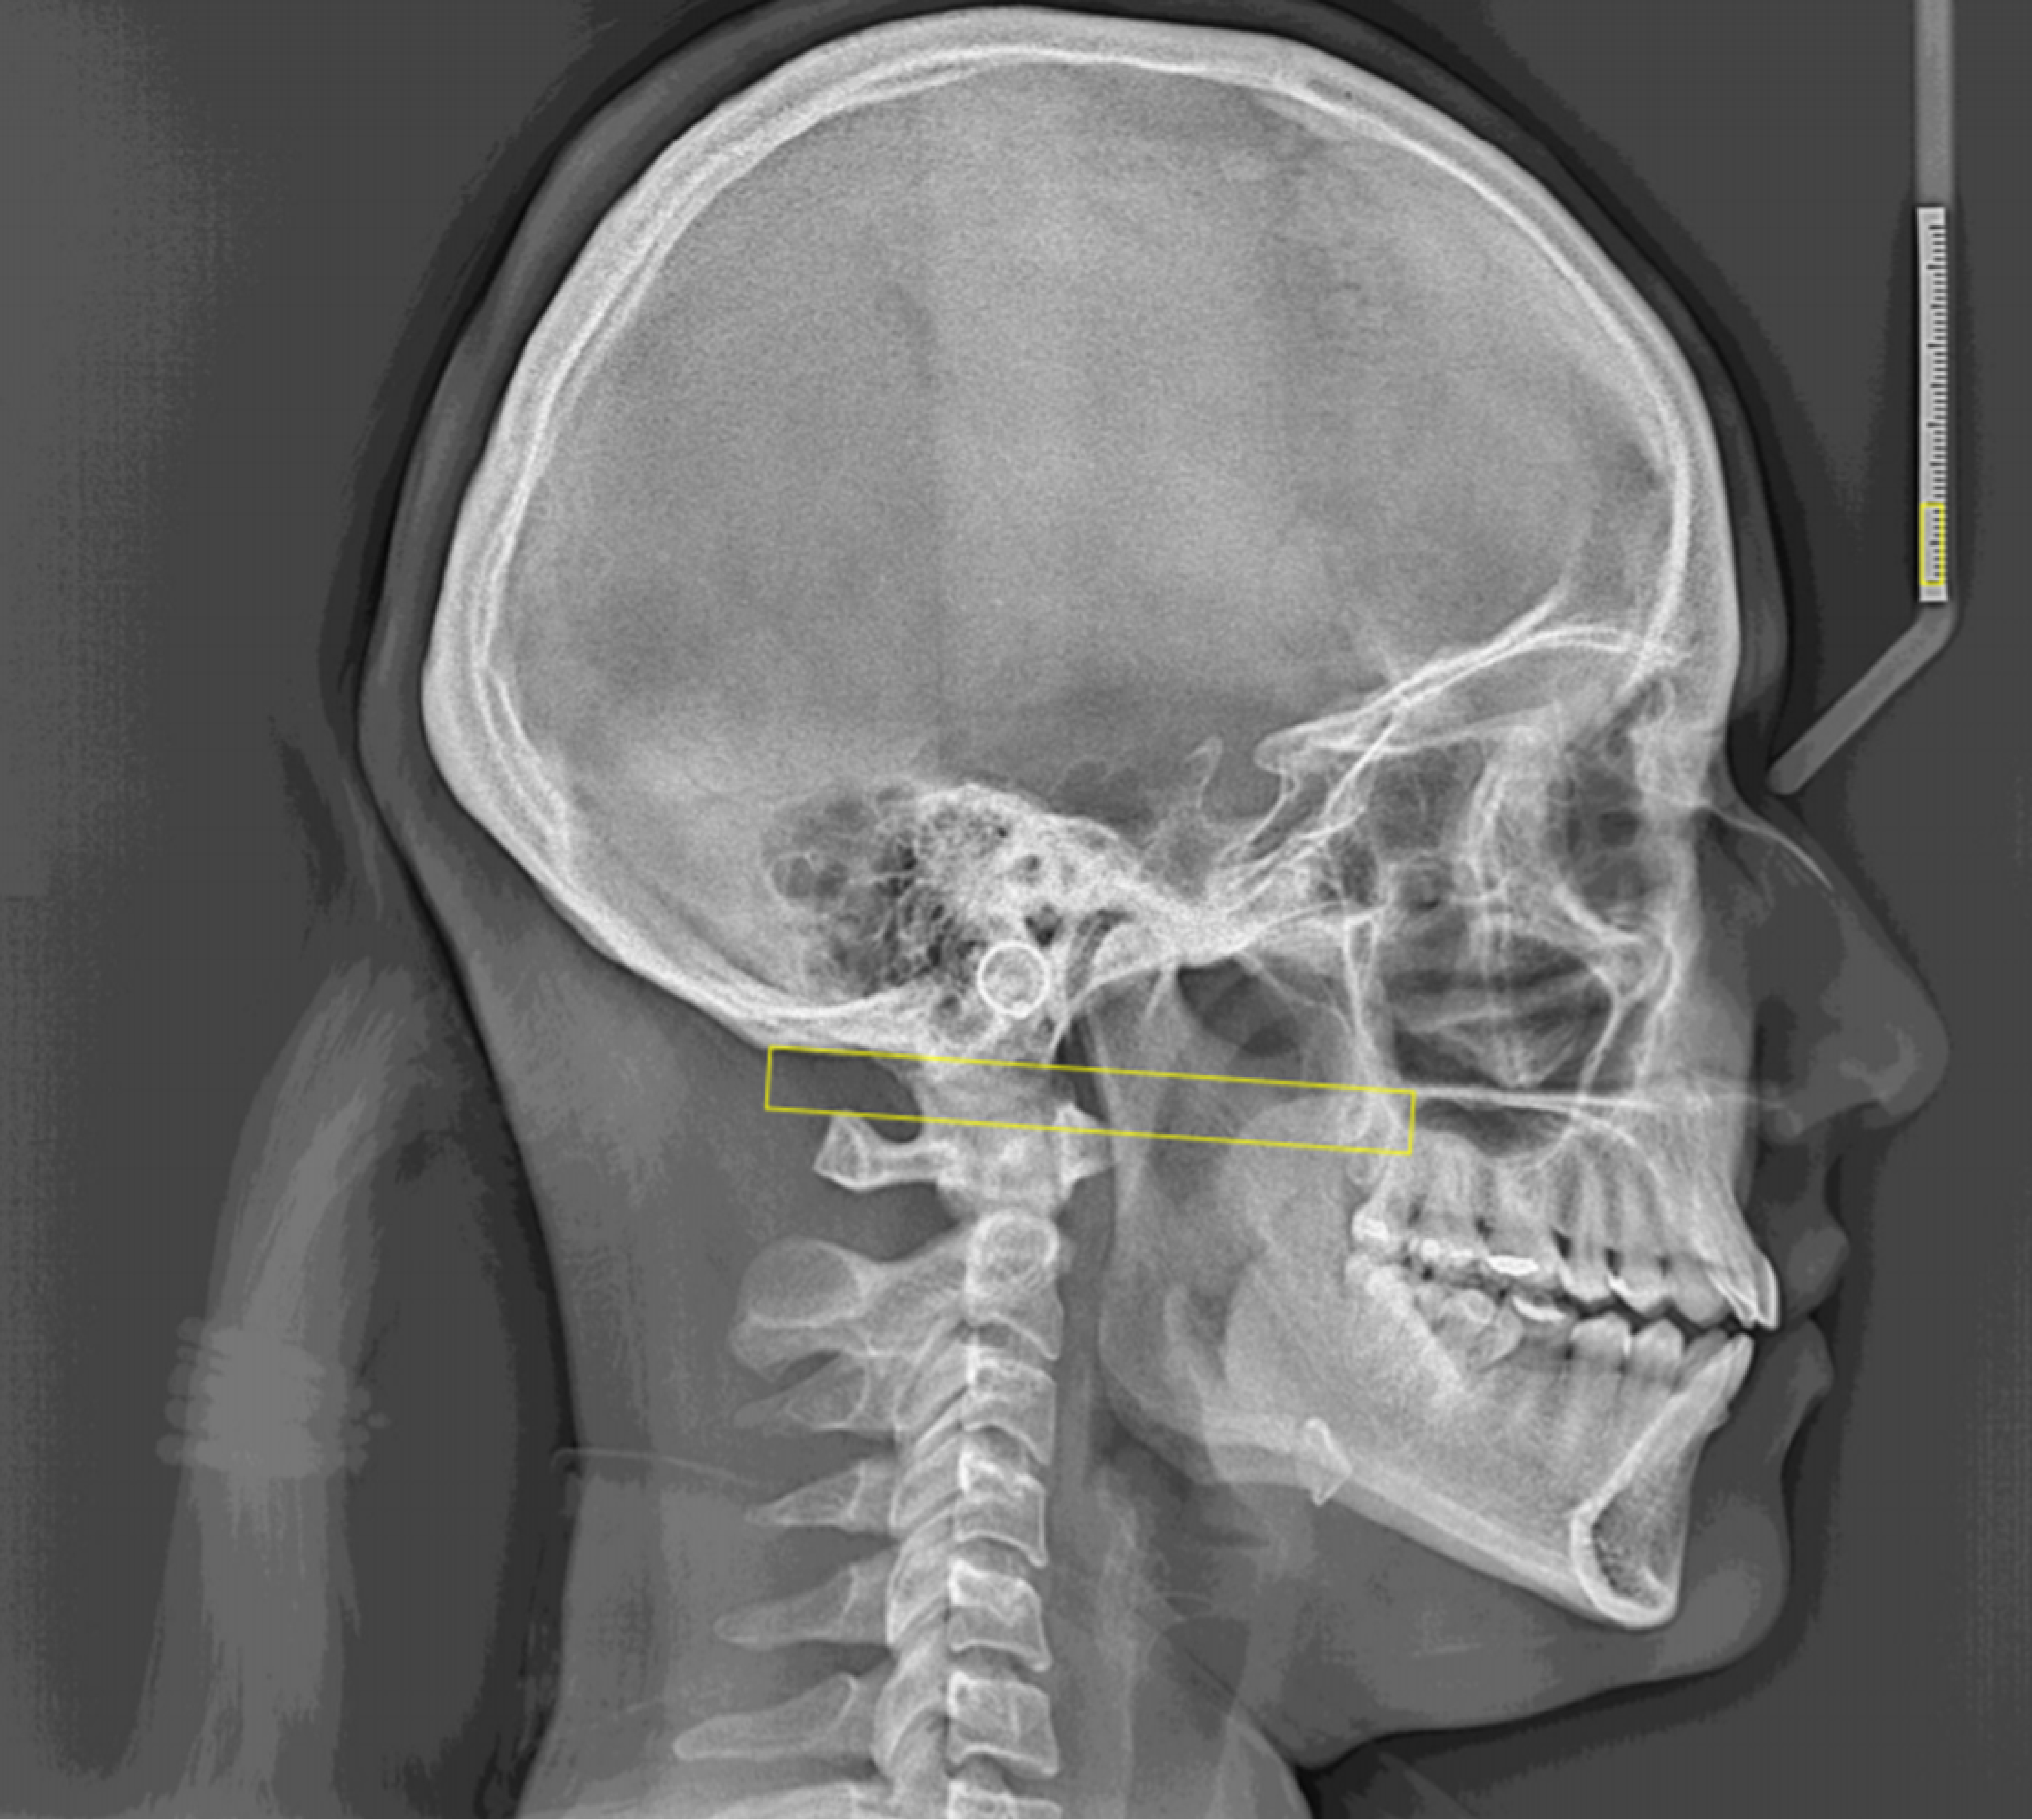

Después, se realizó una consulta con un odontólogo, quien derivó al procedimiento de telerradiografía lateral para la medición del espacio C0-C1, siguiendo el trazado cefalométrico propuesto por Mariano Rocabado.

Para la medición del espacio suboccipital C0-C1 se utilizó un equipo de telerradiografía lateral de imágenes digitales y la medición según el trazado cefalométrico de Rocabado.9,10 Siguiendo este procedimiento: (i) calibración de la radiografía: se mide la distancia del punto 0 al punto 10 mm y se establece una proporción por medio de una fórmula en hoja de cálculo para las medidas que se obtengan midiendo en la radiografía; (ii) ubicar el punto occipital, espina nasal posterior y arco superior del atlas: se agregó un objeto con forma de punto para ubicar los planos mencionados; (iii) se procede a trazar un plano conformado por los puntos occipital y espina nasal posterior (plano McGregor): agregar un objeto con forma de rectángulo y ubicar la base superior en el plano McGregor; (iv) se traza una línea perpendicular al plano de McGregor utilizando el punto del arco superior del atlas: estirar el rectángulo hasta el punto superior del atlas; y (v) se procede a medir la línea generada en el paso (iii): abrir las propiedades del objeto rectangular y obtener la medida del alto del rectángulo y colocar el valor en la fórmula generada en la hoja de cálculo generada en el paso (i) para obtener el valor real del C0-C1 (Figura 1).